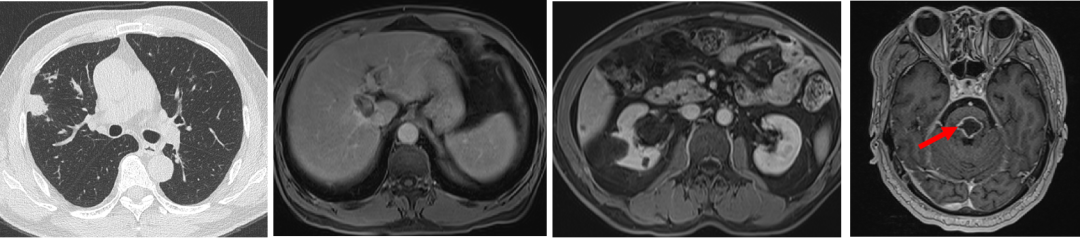

2019年3月胸部CT:右肺上叶近水平裂胸膜处有一枚结节,大小约6mm*5mm,考虑肿瘤转移;腹部MRI:肝右叶S8段新发结节,弥散受限,约16mm*12mm,考虑转移瘤可能性大。

诊断:1. 右半结肠癌术后(pT3N1bM0)化疗后进展(肝,肺?),(RAS、BRAF 野生型,pMMR);2. 高血压病。

目前诊断为右半结肠腺癌术后肝肺转移;

患者为异时性复发;

目前为寡转移:肝脏病灶一个,肺部病灶一个;

肝脏病灶位于S8段,上下骑跨动脉,难以手术切除,考虑射频消融治疗;

肺部病灶可能为转移灶,小于1cm,可密切观察。积极处理的话,考虑手术为首选。

2019.4.10于介入科行肝S8段转移瘤射频消融术。

患者拒绝肺部病灶手术治疗,选择观察等待。

2019.4.24 行FOLFIRI方案化疗1周期,期间出现II度血小板减少,后患者拒绝继续化疗。

因肝脏转移瘤靠近血管,射频消融术后复查CT认为肿瘤边缘存在强化,2019.5.27 行肝S8段转移瘤放疗,DT 40GY/5F。

2019年9月复查,右肺结节略增大,由6mm变成9mm,肺部单个转移灶建议患者手术,病人拒绝,继续选择观察。

2019年10月患者出现头晕严重,不能下床独立行走,伴额头及右侧肢体麻木。

2019.10.18 当地医院头部MRI示:脑干区异常信号,约11mm*15mm,考虑转移瘤合并脑卒中。

脑部蛋氨酸PET示:脑桥结节,蛋氨酸代谢异常增高,SUVmax 4.51,考虑转移性恶性肿瘤。

影像科、神经内科会诊,考虑脑部病灶为肠癌转移病灶。